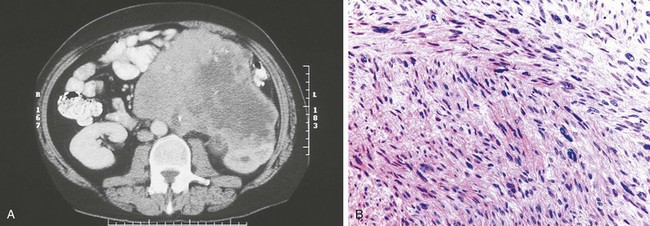

RCC in von Hippel-Lindau disease differs from its sporadic counterpart in that the diagnosis is made at a young age and there are usually multiple bilateral renal tumors (Maher and Kaelin, 1997; Uzzo and Novick, 1999; Zbar et al, 1999; Grubb et al, 2005a; Nathanson and Stephenson, 2009). Although these are generally low-stage tumors, they are capable of progression to metastasis and represent a frequent cause of death in patients with von Hippel-Lindau disease. RCC in these patients is characterized histopathologically by both solid tumors and renal cysts that contain either frank carcinoma or a lining of hyperplastic clear cells representing incipient carcinoma (Fig. 49–24) (Christenson et al, 1982; Walther et al, 1995; Nathanson and Stephenson, 2008). Therefore, adequate surgical treatment of localized RCC in von Hippel-Lindau disease requires excision and/or ablation of all solid and cystic renal lesions whenever feasible (Grubb et al, 2005a; Nathanson and Stephenson, 2008). Choyke and colleagues (2001) have shown that intraoperative ultrasonography may be a valuable adjunct for this population of patients. In their series this study identified additional tumors in 25% of patients with hereditary renal cancer undergoing renal exploration.

Figure 49–24 A, CT scan after administration of contrast agent shows bilateral solid and cystic renal masses in patient with von Hippel-Lindau disease. B, Histopathologic section of one of the renal cysts shows lining of clear cells representing incipient carcinoma.